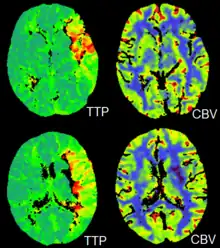

CT perfusion imaging

CT perfusion imaging is a specific form of CT to assess flow through blood vessels whilst injecting a contrast agent.[21] Blood flow, blood transit time, and organ blood volume, can all be calculated with reasonable sensitivity and specificity.[21] This type of CT may be used on the heart, although sensitivity and specificity for detecting abnormalities are still lower than for other forms of CT.[22] This may also be used on the brain, where CT perfusion imaging can often detect poor brain perfusion well before it is detected using a conventional spiral CT scan.[21][23] This is better for stroke diagnosis than other CT types.[23]